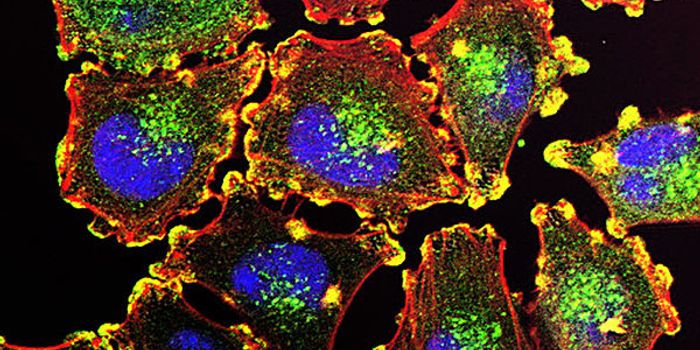

FEB 24, 2016Clinical & Molecular DXCancer cells are exquisitely cunning – they mutate and adapt to escape the body’s own defense mechanisms, an ...

NOV 15, 2016CancerCellular aging is thought to be controlled, in part, by the chromosomes’ telomeres – end caps that protect o ...